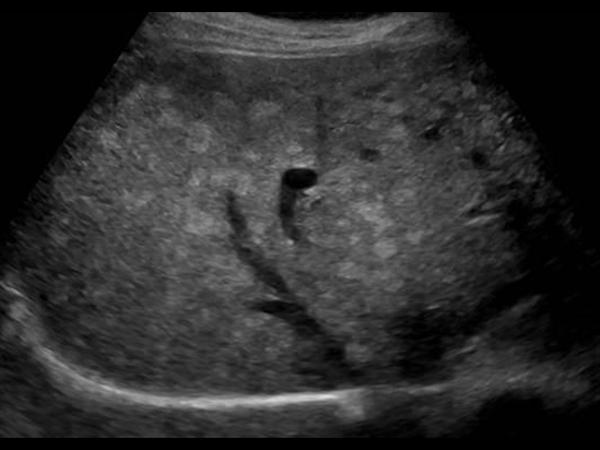

Gan nhiễm mỡ - Ảnh 4

Gan nhiễm mỡ

» Thông tin: Nữ giới – 59 tuổi.

» Lâm sàng: Kiểm tra sức khỏe.